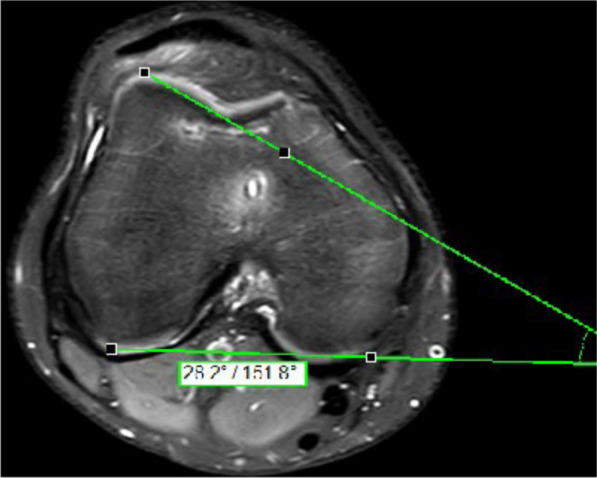

Methods: A total of 83 trochleoplasties in 83 patients were performed between 2014 and 2021 in one institution. Surgical indications for trochleoplasty were recurrent patellofemoral instability and a lateral trochlear inclination angle (LTI) ≤ 11˚ and a trochlear depth ≤ 6 mm. Of the trochleoplasties, 40 were done by open technique (OT) and 43 by arthroscopic technique (AT). In every case an additional medial patellofemoral ligament (MPFL) reconstruction was performed. Additional tuberosity tibia transfer and/or de-rotation of the femur were done when indicated. Pre- and postoperative magnetic resonance imaging (MRI) were analyzed in respect to LTI, trochlear depth, and lateralization of the patella. Postoperative subjective clinical assessment was done using the Kujala Score, Banff II Score, Tegner Score, and Marx Score.

Results: Of the patients, 15 with OT and 20 with AT were available for follow-up. The mean follow-up was 29.9 months in the OT group and 12.7 months in the AT group. No re-dislocation was observed in either groups. A significant reduction of LTI, increase of trochlear depth, and a reduction of lateralization of the patella was observed between the pre- and postoperative MRI scans in both groups. No significant difference in the observed MRI parameters was found between the two groups. Neither was there a difference in the postoperative Kujala Score, Banff II Score, Tegner Score, and Marx Score between the two groups. Length of stay was on average 6.2 days in the AT group and 8.1 days in the OT group. The surgical time was on average 141 min in the OT group and 160 min in the AT group.